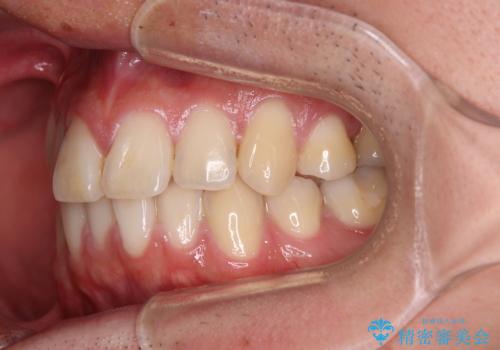

インビザライン・モデレートは、製作できるアライナーの枚数に制限があるため、移動可能な量に限りがあるものの、インビザライン・ライトよりも枚数が多いため、幅広い症例に対応可能です。